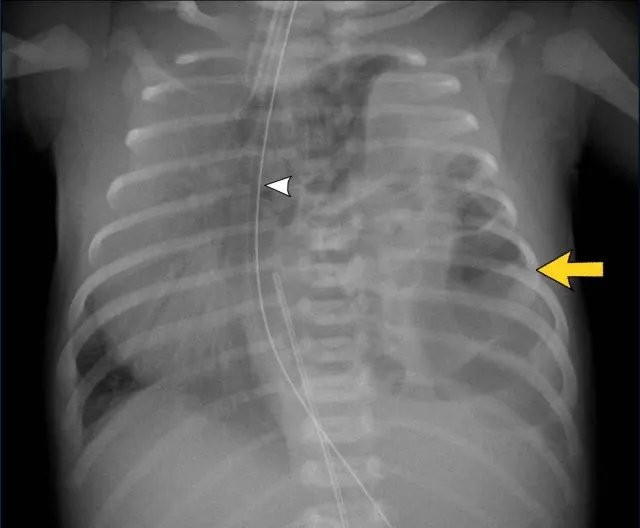

- Pneumothorax: Air in pleural space. Lucency, absent markings, visceral pleural line. Deep sulcus sign (supine).

- Chest Tube (ICD):

- Pneumothorax: Apical. Effusion: Basal.

- All side holes within pleural space.